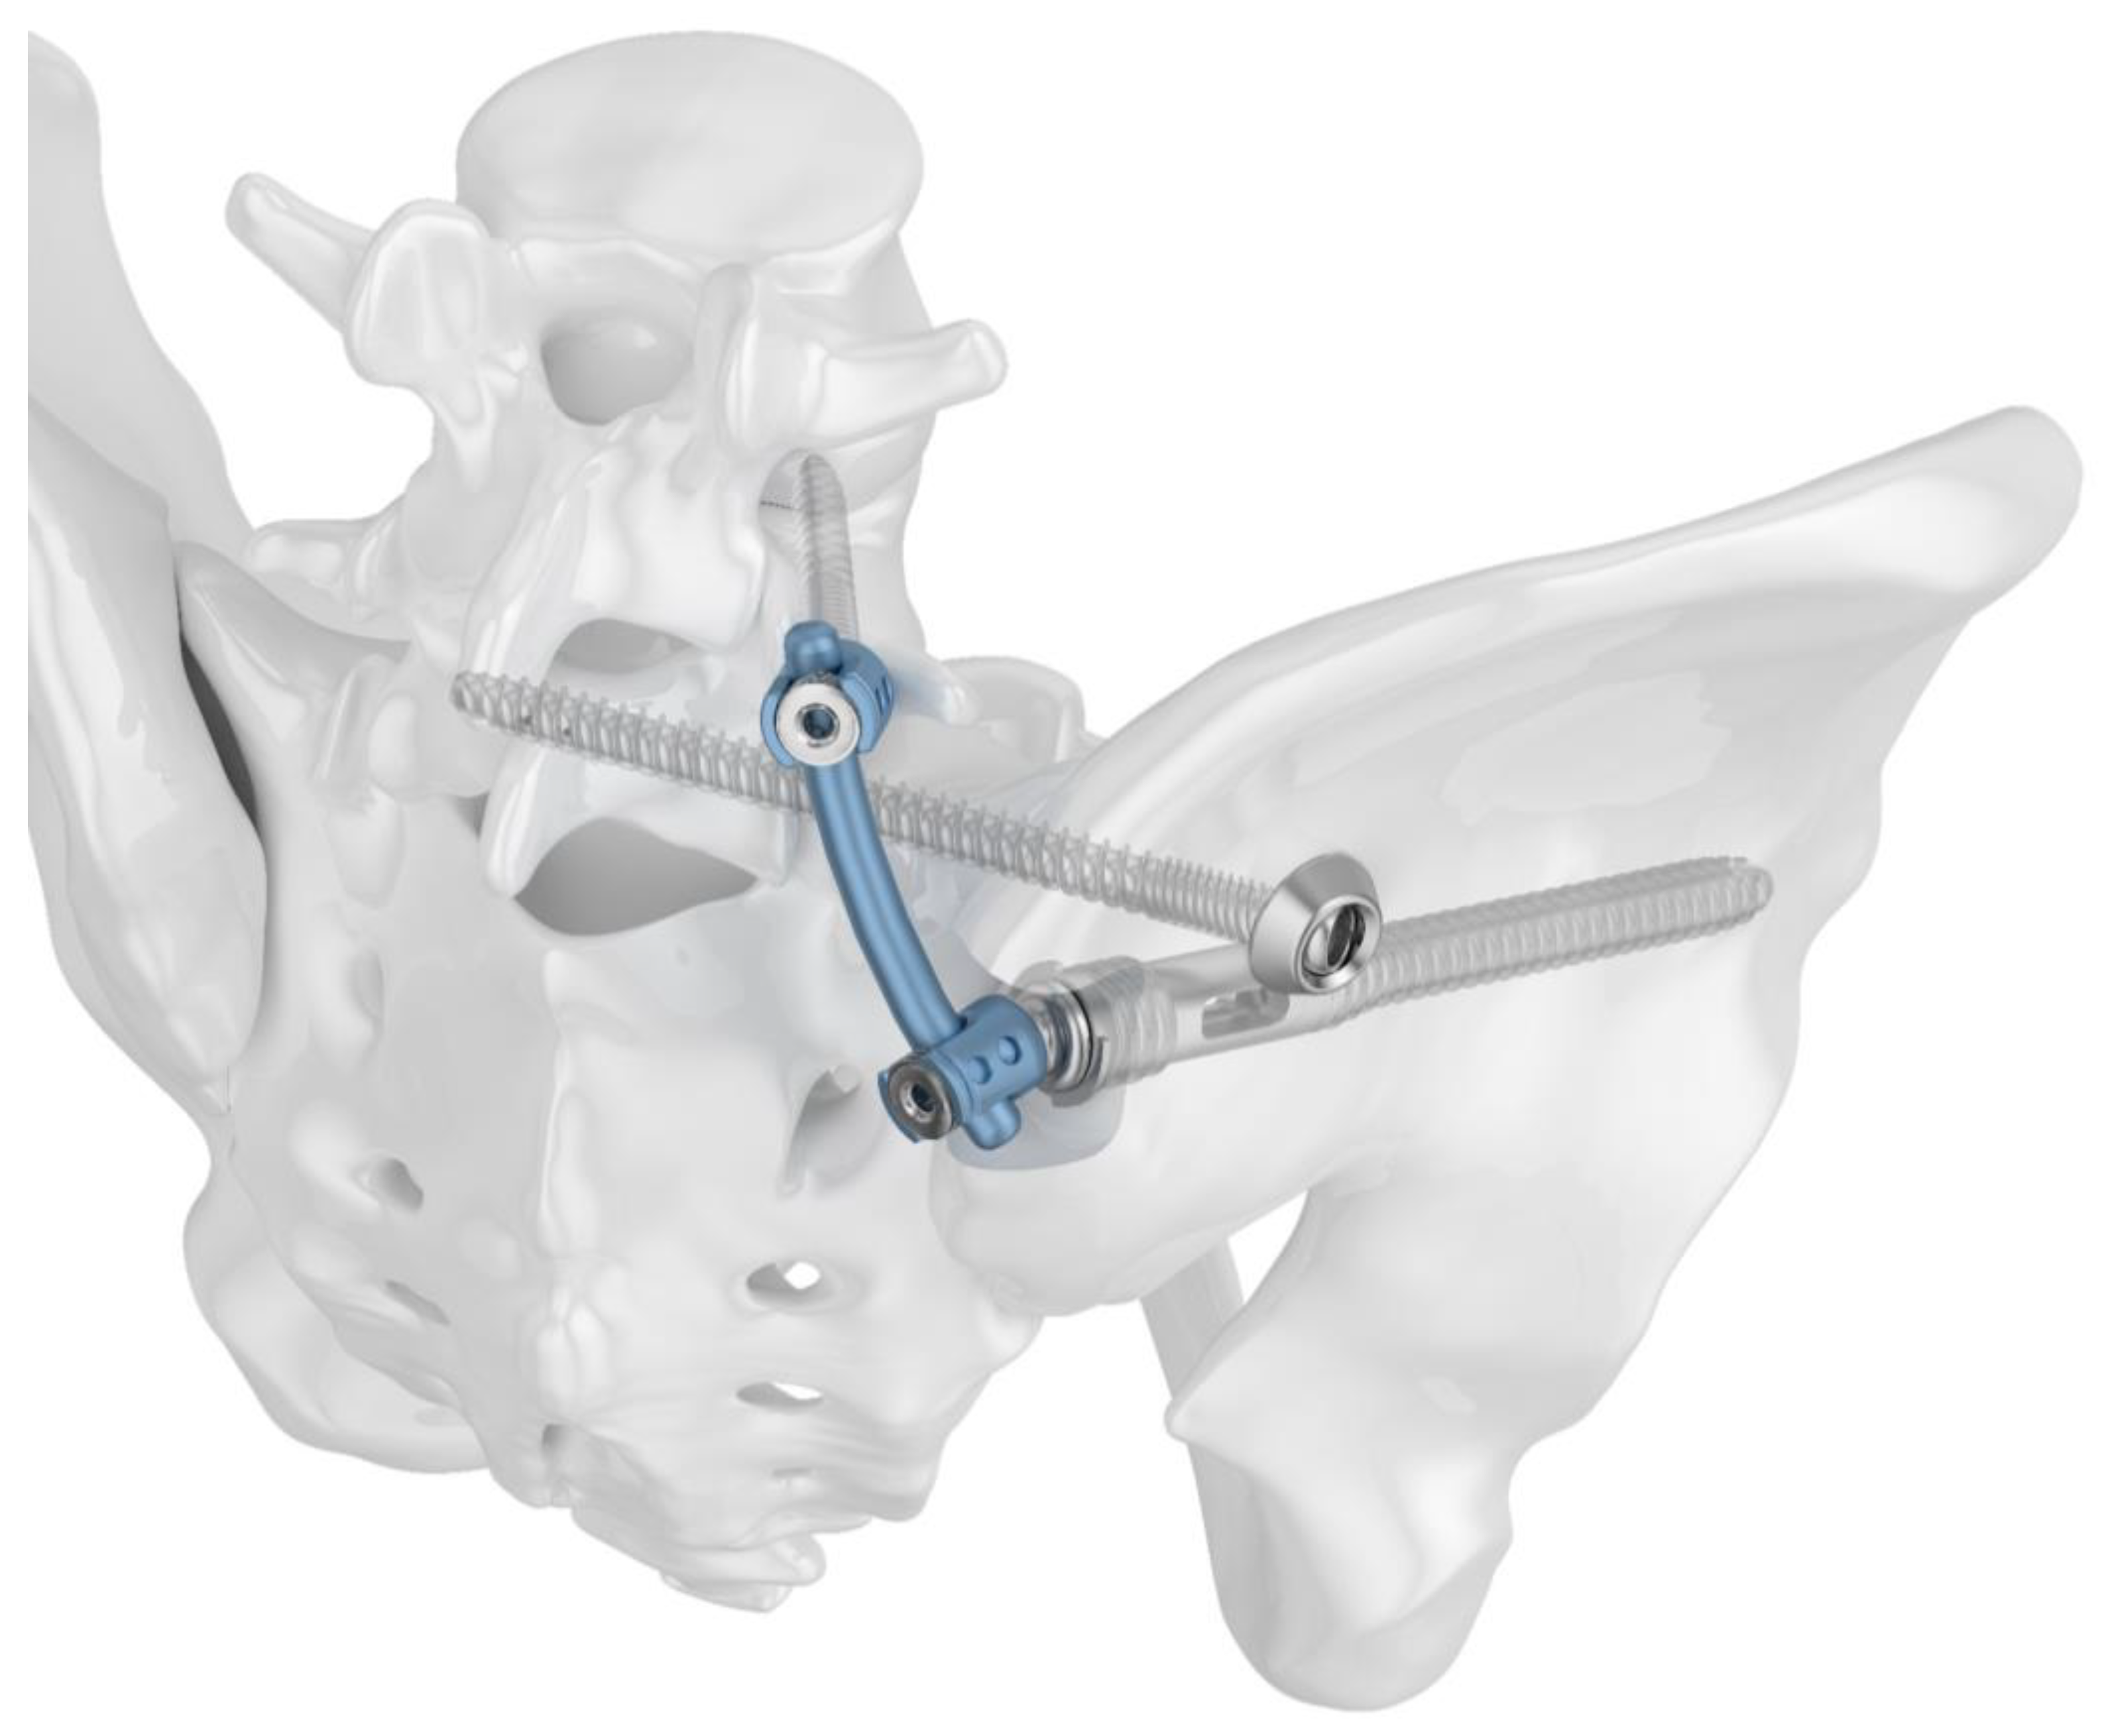

Figure 2.

Image visualizing the configuration of Group II (TF): in contrast to Group I, the iliosacral screw is placed separately from the iliac screw in a more cranial position.